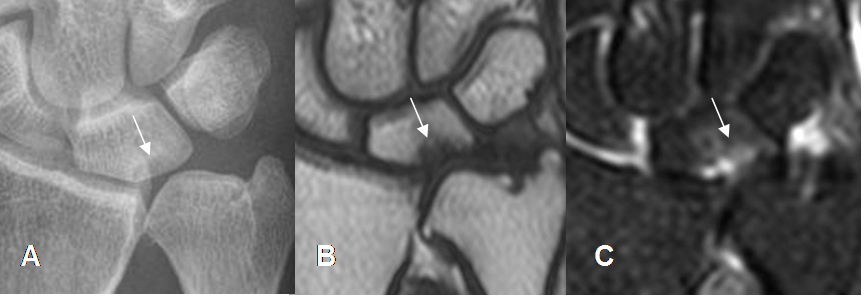

Fig 84. Impactación ulnar.

A: Rx AP. Varianza ulnar positiva, que erosiona en hueso semilunar.

B: RM coronal en T1 y B: RM coronal en STIR. Lesión osteocondral del semilunar, por pinzamiento ulnar.